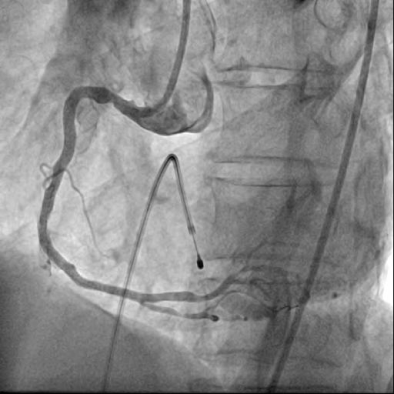

급성 하벽 ST분절 상승 심근경색에 합병된 완전방실차단으로 진단하고, 신속하게 일시적 심박동기를 우심실에 삽입하여 박동수를 회 복시킨 뒤에 관상동맥 조영술을 하였다. 우관상동맥의 심한 협착과 혈전으로 인한 급성 폐색을 확인하고 (그림 2, 동영상 1), 풍선카테 터와 스텐트를 이용한 일차적 관상동맥중재술을 통해 재관류치료를 하였다 (그림 3, 동영상 2).

재관류치료 후 환자는 동리듬을 회복하였고(그림 4), 혈압과 맥박수는 안정되어 환자는 무사히 퇴원하였다.